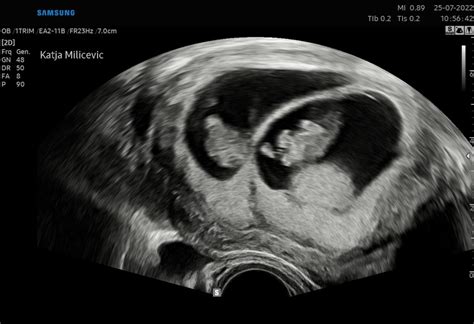

- Nosečnost: Simptomi se lahko pojavijo po izostanku menstruacije ali okoli časa implantacije (ugnezditve oplojenega jajčeca v maternično steno), približno 6-12 dni po spočetju. Ti simptomi običajno ne izginejo z začetkom menstruacije, ampak lahko vztrajajo v prvem trimesečju nosečnosti. Če simptomi ostanejo ali se celo povečajo po izostanku pričakovane menstruacije, je to bolj značilno za nosečnost.

Če imate simptome, ki so značilni za PMS, menstruacija pa je izostala in obstaja možnost, da ste noseči, je najzanesljivejši korak opravljanje zgodnjega testa nosečnosti. Ti testi zaznavajo prisotnost nosečniškega hormona hCG (human chorionic gonadotropin) v urinu, ki ga telo začne proizvajati po ugnezditvi oplojenega jajčeca.

Če je test pozitiven, se naročite pri svojem ginekologu za potrditev nosečnosti in nadaljnje svetovanje. Če je test negativen, a simptomi vztrajajo in menstruacija še vedno izostaja, ponovite test čez nekaj dni ali se posvetujte z zdravnikom.